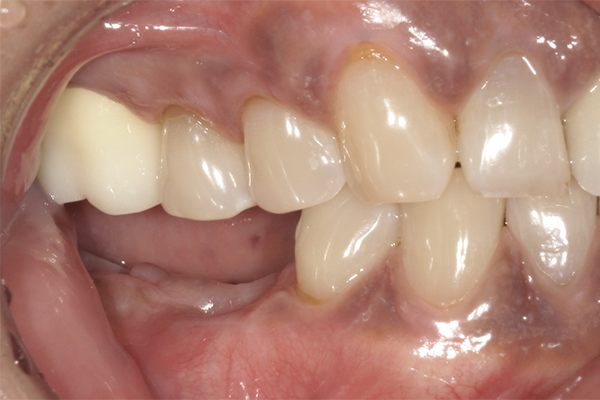

| 主訴 | 奥歯で噛めない、顎が痛い |

|---|---|

| 治療内容 | 奥歯のインプラント治療、前歯・奥歯の被せ物治療 |

| 治療期間 | 6ヶ月 |

| 治療費 | 350万円 |

| 治療リスク | 被せ物をつけた初期の段階で歯がしみることがある(時間とともに改善する) インプラント治療後に3日程度痛みと腫れを伴うことがある |